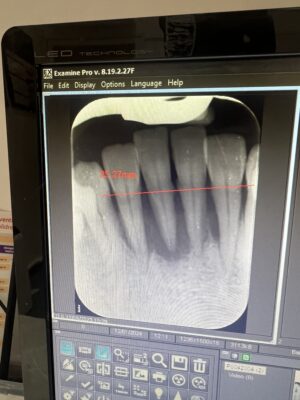

• Quite a challenging case here, what would you do for this lower anterior sector. The two lower central incisors were extracted 6 months ago and the area has healed but still vertical bone loss is observed. Here is a video of the cbct scan.

Options to do:

– extractions of lower laterals followed by vertical and horizontal bone grafting…